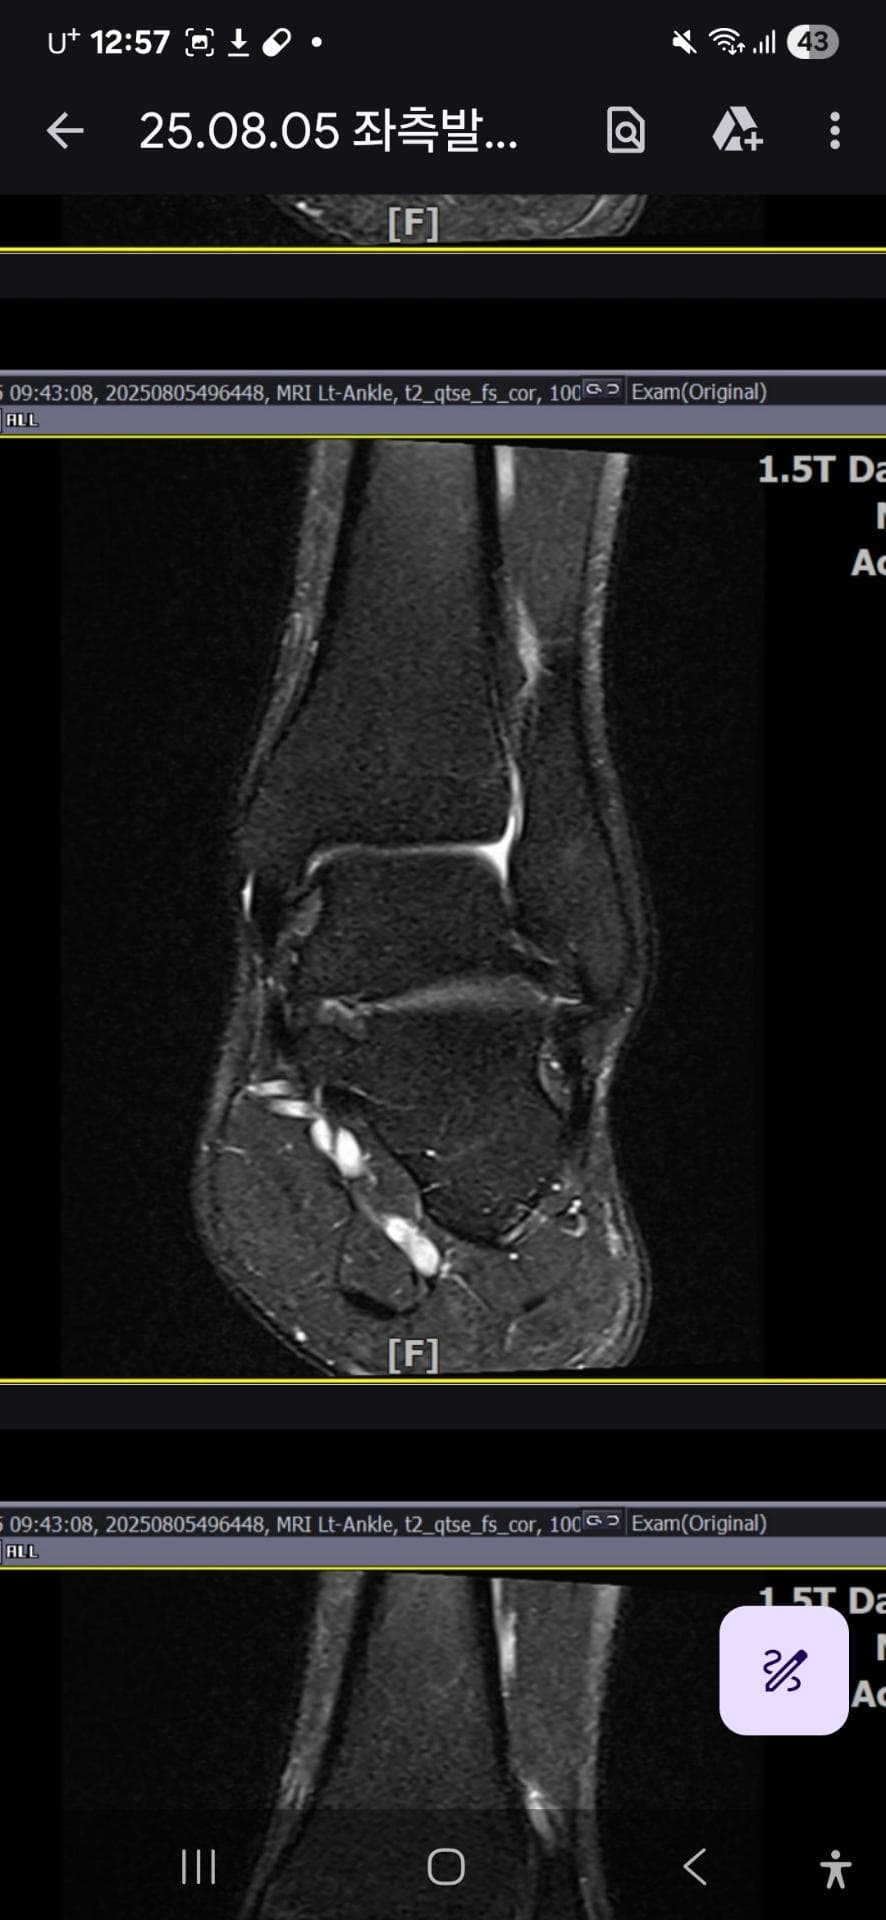

그래도 통증이 남아 8월 5일에 MRI를 촬영했는데, 병원에서는 “인대는 이어져 있고, 이 정도면 재활운동으로 호전될 것”이라는 설명을 들었습니다.

MRI 상 전거비인대와 발목 상태가 정말 회복 단계인지, 아니면 만성으로 넘어가는 건 아닌지 전문가분들의

의견을 듣고 싶습니다.

mri 사진(8월 촬영)상 인대가 호전됬는지도

알고 싶습니다.

올려주신 mri를 보면 전거비인대는 연속성이 유지되고 있고 파열이나 큰 손상 흔적은 없어 재활로 회복 가능한 상태로 보입니다 다만 3개월 가까이 활동 시 통증과 미열감이 남아 있는 것은 조직 회복이 아직 완전히 끝나지 않았거나 주변 연부조직 관절 움직임 제한 등으로 인한 과민 반응일 수 있습니다.

초음파와 비교하면 mri 상으로 인대 연속성이 확인되므로 심각한 악화나 재파열은 아닌 것으로 판단됩니다

MRI상에서는 인대의 회복이 이루어지고 있는 덧으로 보이지만 인대의 회복은 소요되는 시간이 오래 걸리고, 주변 근육의 약화나 기능 저하로 인해 통증이나 불편감이 지속될 수 있습니다.